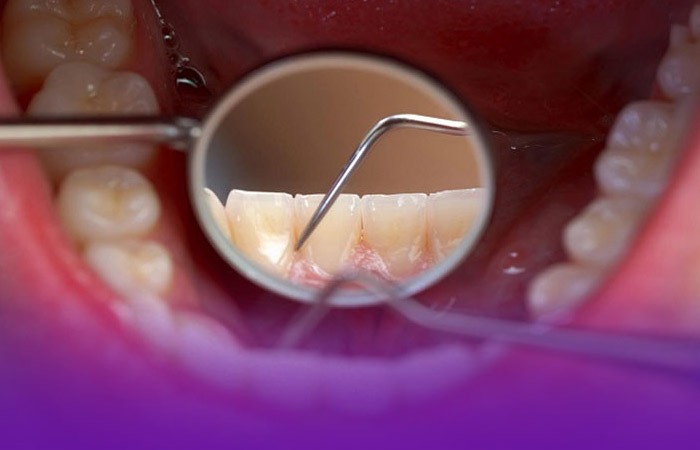

درچندسال گذشته،با افزایش تعداد دانشکده‌های دندانپزشکی،آمار فارغ‌التحصیلان این رشته به‌مراتب بیشتر از قبل شده است.این روند به‌حدی رسیده که دیگر عملا جای خالی برای دندانپزشکان در مراکز استان‌ها و شهرهای بزرگ وجود ندارد و فرصت برای پیگیری سلامت دهان و دندان برای شهروندان بسیار بالا رفته‌‌. اما آنچه واقعا نگران‌کننده است، این‌که با وجود آمار مناسب دندانپزشکان و البته با آموزش‌ها و پویش‌هایی که در مدارس و محیط‌های آموزشی اجرایی می‌شود، آمار پوسیدگی، از دست دادن دندان و پرشدگی و سایر بیماری‌های دهان و دندان، روز به روز در حال افزایش است.

به نظر می‌رسد علت‌ اصلی این وضعیت موقتی و مقطعی بودن پویش‌ها و آموزش‌هایی است که ارائه شده، چون ما هیچ‌وقت به آموزش مستمر و همیشگی پایبند نبوده‌ایم. البته طبیعتا وجود همان آموزش‌های کوتاه و مقطعی هم بسیار ارزشمند است اما کافی نیست. تجربه نشان داده مسأله بهداشت دهان و دندان، برخلاف بسیاری از بیماری‌ها، یک فرآیند مداوم پیشگیری است و نه یک درمان مقطعی. این موضوع همانند عادت‌های رفتاری، نیازمند تکرار و نهادینه‌سازی در ساختارهای زندگی روزمره فرد است. درواقع آموزش‌های مقطعی مانند یک سخنرانی در مدرسه یا یک پوستر در مطب تأثیر کوتاه‌مدت دارد اما برای جلوگیری از پوسیدگی، مسواک زدن صحیح، استفاده از نخ دندان و انتخاب‌های تغذیه‌ای مناسب، باید به عادت‌های ناخودآگاه افراد تبدیل شود. پیام‌های بهداشتی باید به محیط‌هایی نفوذ کند که مردم معمولا آنها را با پیام‌های آموزشی مرتبط نمی‌دانند. اگر شخصیت کودک در یک فیلم، روزی دوبارمسواک بزند،این رفتار بهداشتی درذهن مخاطب به‌عنوان رفتاری پذیرفته‌شده جای می‌گیرد.آنچه روشن است این‌که اگر پیام‌ها و آموزش‌های مورد نیاز جامعه درسطوح مختلف جامعه تکرارشود،ماندگاری بیشتری دارد.از طرف دیگر، برخی اقدامات عملی هم درمحیط مدرسه انجام می‌شودکه جامعیت نداردوبه‌صورت نصف ونیمه پیش می‌رود؛نمونه‌اش اقدام تحسین‌برانگیز فلورایدتراپی است که فقط در برخی مدارس انجام می‌شود. یاحتی دربرخی فصول فراموش می‌شودوطبیعتا اقدام مفیدی مانند فلورایدتراپی، اگر به صورت مقطعی و ناقص اجرا شود وپشتوانه آموزش مستمر نداشته باشد، نمی‌تواند روند افزایشی پوسیدگی دندان‌ها را متوقف کند. در این میان فراموش نکنیم که آموزش باید به والدین نیز داده شود؛ والدینی که خودشان باید بیاموزند چطور به‌درستی به کودکان خود مسواک زدن، نخ دندان کشیدن و استفاده از دهانشویه راآموزش دهند.همچنین آگاهی‌بخشی درباره تغذیه کودکان، تنوع و دفعات مصرف خوراکی‌ها و لزوم جایگزین کردن تنقلاتی که پوسیدگی کمتری ایجاد می‌کند، نیازمند برنامه‌ای آموزشی با ویژگی طولانی‌مدت است؛ که در اغلب اوقات، نادیده گرفته می‌شود. به نظر می‌رسد این مسئولیت، همگانی است و تنها با جریان آموزشی مداوم و فراگیر می‌توانیم انتظار کاهش آمار پوسیدگی دندان در نسل‌های آینده را داشته باشیم.